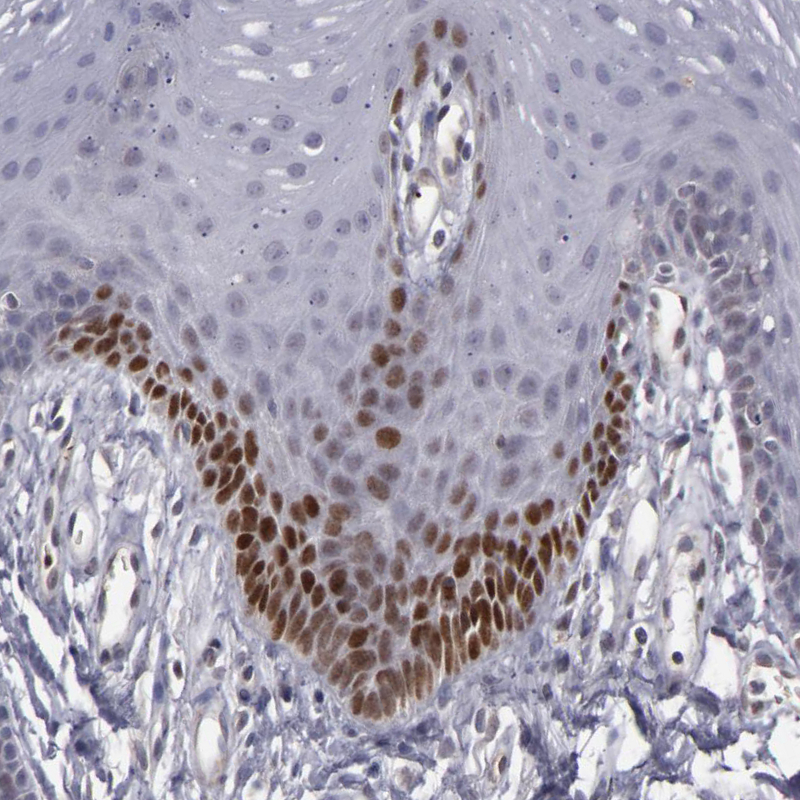

Immunohistochemical staining of human oral mucosa shows moderate nuclear positivity in subset of squamous epithelial cells.